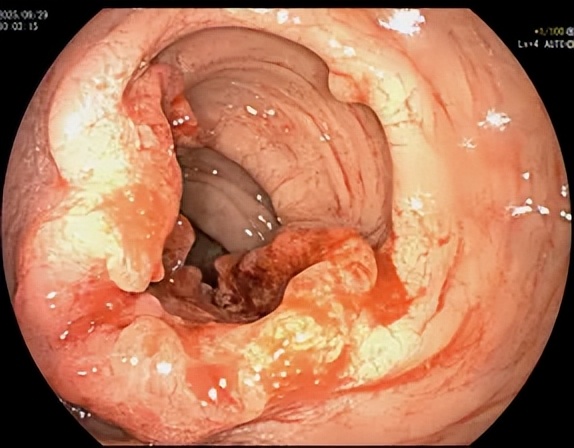

當(dāng)內(nèi)鏡進(jìn)入腸道,景象讓唐瀟醫(yī)生心里一沉:十年前的乙狀結(jié)腸和直腸息肉,已從可輕松摘除的“小疙瘩”,演變成形態(tài)不規(guī)則、質(zhì)地脆爛、極易出血的癌性病灶。

10年后,同一位置的乙狀結(jié)腸息肉已發(fā)生明顯癌變,表面潰爛、壞死。